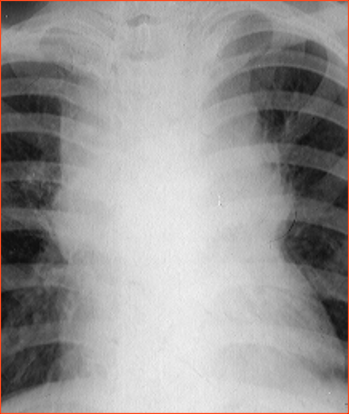

Rx toracică, incidență P-A

DESCRIERE:

la niv. întregului hemitorace drept → opacitate extinsă, nesistematizată, de intensitate mare, omogenă

caracter expansiv → împinge traheea și mediastinul de partea opusă

diafragm deplasat în jos

lărgirea spațiilor intercostale

umplerea spațiului costo-diafragmatic

DX: pleurezie masivă

DD: atelectazie → caracter retractil